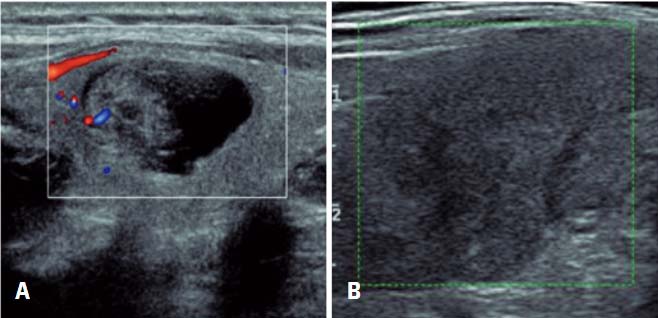

Correlation of Thyroid Imaging Reporting and Data System [TI-RADS] and fine needle aspiration: experience in 1,000 nodules

To correlate the Thyroid Imaging Reporting and Data System (TI-RADS) and the Bethesda system in reporting cytopathology in 1,000 thyroid nodules.

A retrospective study conducted from November 2011 to February 2014 that evaluated 1,000 thyroid nodules of 906 patients who underwent ultrasound exam and fine needle aspiration.

A significant association was found between the TI-RADS outcome and Bethesda classification (p<0.001). Most individuals with TI-RADS 2 or 3 had Bethesda 2 result (95.5% and 92.5%, respectively). Among those classified as TI-RADS 4C and 5, most presented Bethesda 6 (68.2% and 91.3%, respectively; p<0.001). The proportion of malignancies among TI-RADS 2 was 0.8%, and TI-RADS 3 was 1.7%. Among those classified as TI-RADS 4A, proportion of malignancies was 16.0%, 43.2% in 4B, 72.7% in 4C and 91.3% among TI-RADS 5 (p<0.001), showing clear association between TI-RADS and biopsy results.

The TI-RADS is appropriate to assess thyroid nodules and avoid unnecessary fine needle aspiration, as well as to assist in making decision about when this procedure should be performed.